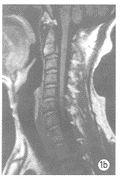

图1 病例1,男,35岁;

图1b MRI知状闰C2I度弱前脱位,椎体前缘不齐。

图1c 1d 冠状位、轴位未见骨折线。